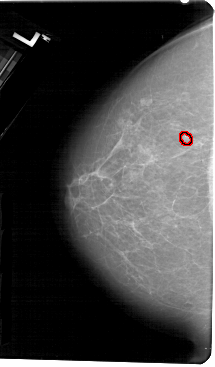

A_1278_1.LEFT_CC

LEFT_CC LINES 5491 PIXELS_PER_LINE 3211 BITS_PER_PIXEL 12 RESOLUTION 43.5 OVERLAY

FILE: A_1278_1.LEFT_CC.OVERLAY

TOTAL_ABNORMALITIES 1

ABNORMALITY 1

LESION_TYPE CALCIFICATION TYPE PUNCTATE DISTRIBUTION CLUSTERED

LESION_TYPE MASS SHAPE OVAL MARGINS ILL_DEFINED

ASSESSMENT 4

SUBTLETY 2

PATHOLOGY BENIGN

TOTAL_OUTLINES 1

BOUNDARY